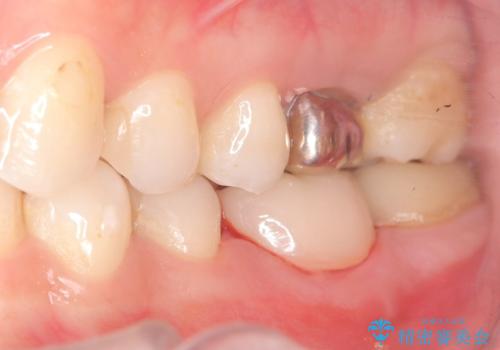

保存が難しい左下6番目の歯を抜歯し、左下8番目の歯(親知らず)を抜歯窩に移植しました。歯牙移植後の動揺防止のため暫間固定を行っています。

骨との定着を確認し、今後矯正治療を行う予定のためレジン冠をセットしています。